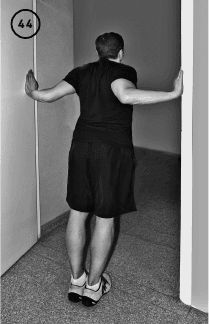

Упражнение «Шарнир – локоть внутрь»

Исходное положение – сидя за столом, обе руки согнуты в локтевых суставах под прямым углом, помещаются предплечьями на стол и упираются локтями в стол, подобно шарниру.

Правая кисть сжата в кулак, левая обхватывает ее снаружи.

Фаза изометрического напряжения: вы пытаетесь привести правый кулак внутрь, опираясь на локоть, как на шарнир. Лева я рука препятствует этому движению.

Удерживаете состояние изометрического напряжения в течение 20–30 секунд.

Фаза растяжения: помещаете руки на края дверного проема и, подаваясь туловищем вперед, 10–20 секунд растягиваете грудные мышцы, которые до этого напрягались. Повторить 1–3 раза. Выполнить для противоположного плеча (ил. 44).